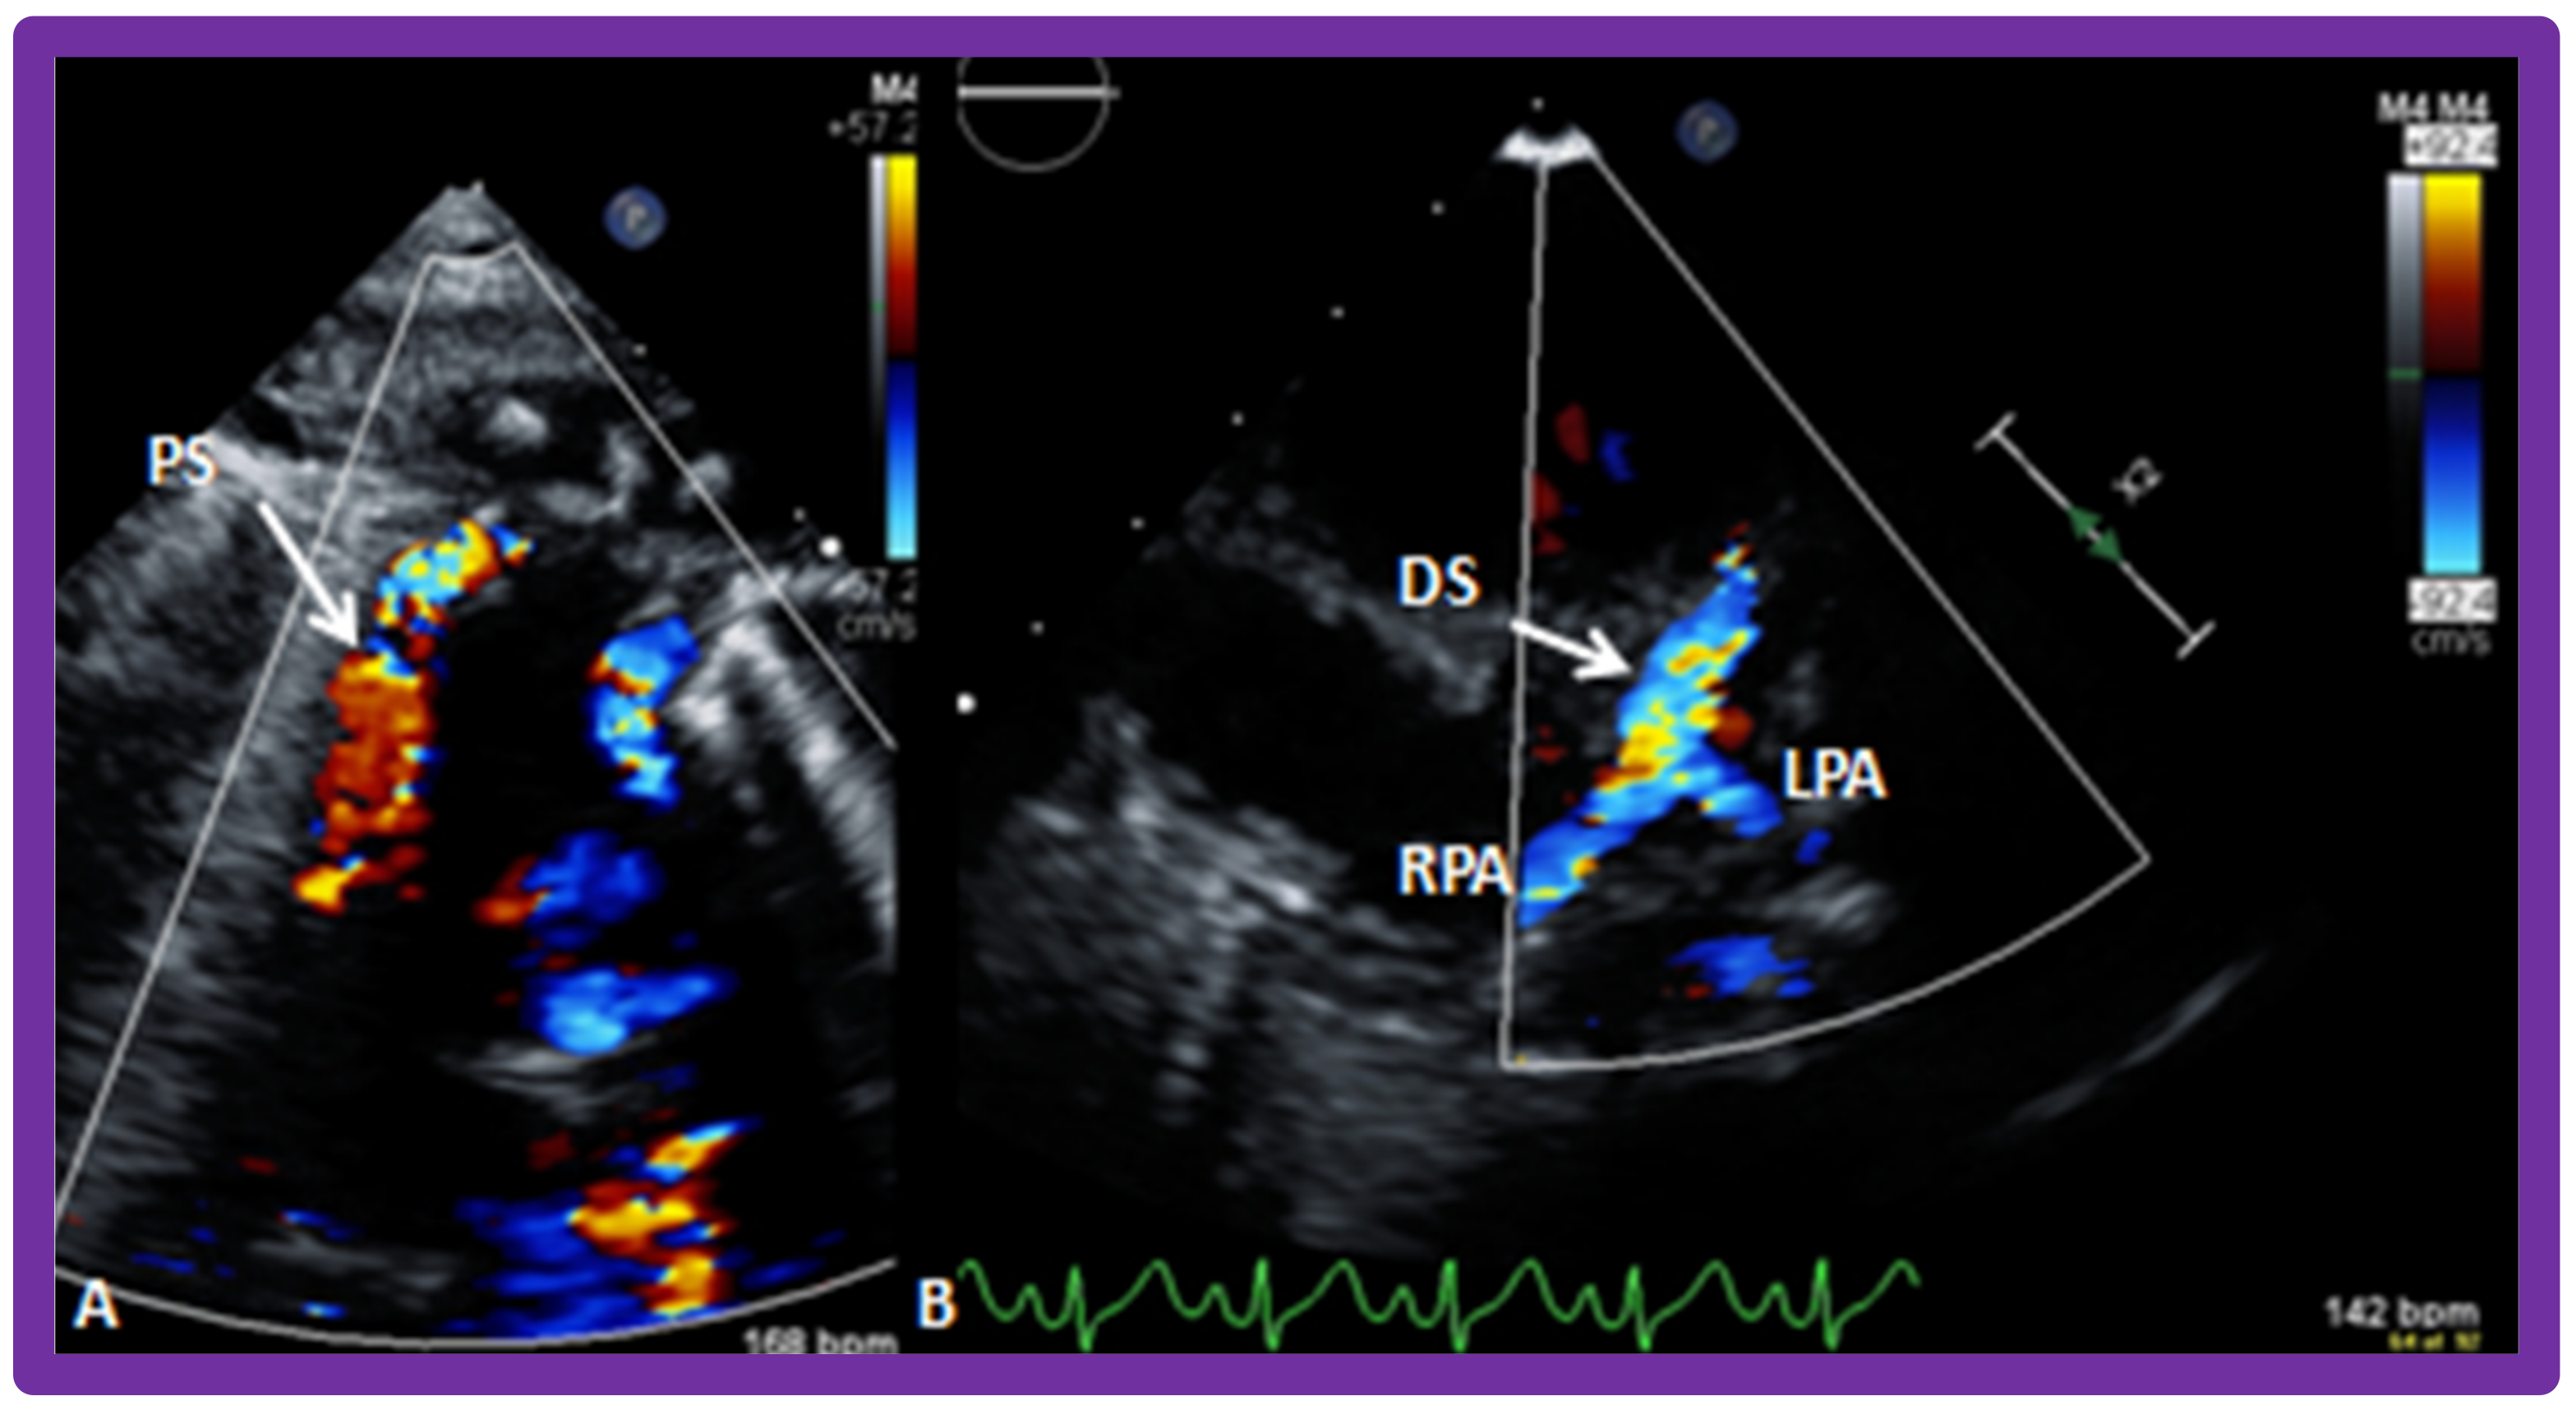

10.1.5. Inter-Ventricular Obstruction

10.2. Stage II